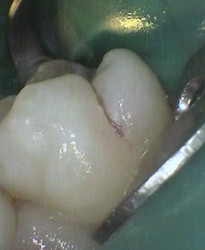

failed sealant has decay restored with white filling

old leaky sealant and decay restored